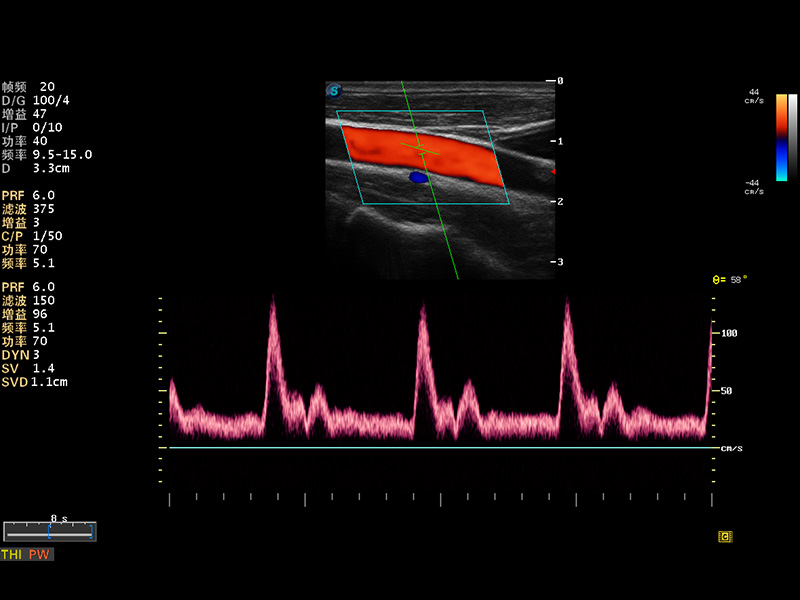

S8 EXP便携式彩色多普勒超声诊断仪是新葡的京集团8814检测站研发的高端全身应用型便携彩超。高通道的VIS平台融合可视化(Visual)、智能化(Intelligent)和人性化(Smart)的特点,配以新葡的京集团8814检测站自主研发生产的探头大家族,使您能够快速、准确的获得病人信息,提高工作效率的同时减轻疲劳。